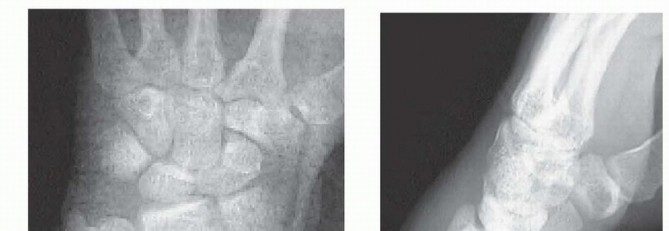

### TECH FIG 2 • A. PA view showing an impacted scaphoid facet fracture fragment with an obvious injury to the SLIL. B. Lateral view showing a dorsal rim fracture fragment. C. The arthroscope is in the 6R portal, demonstrating the impacted scaphoid facet fracture fragment. This would be quite difficult to view through an open arthrotomy but is well visualized arthroscopically under bright light and magnified conditions. D. The impacted scaphoid facet fragment is elevated back to the volar rim, using the rim as a landmark to judge rotation. E,F. Geissler grade III tear involving the SLIL as seen through the 3-4 portal (E) and the radial midcarpal portal (F).(continued) Suspend the wrist in the traction tower, establish portals, and evacuate the fracture debris and hematoma. The depressed lunate facet fragment is best seen with the arthroscope in the 3-4 portal ( TECH FIG 2C,D). Percutaneously place an 18-gauge needle directly over the depressed fragment as viewed arthroscopically. Insert a large K-wire about 2 cm proximal to the previously placed 18-gauge needle to percutaneously elevate the depressed lunate facet fragment.

TECH FIG 2 • (continued) G,H. PA and lateral radiographs showing anatomic reduction to the impacted scaphoid facet fracture. (The tear of the SLIL also was acutely repaired.) Use a bone tenaculum to further diminish the gap between the radial styloid and lunate facet fragments. Place guidewires transversely under the subchondral surface of the radius from the radial styloid into the anatomically reduced lunate facet fragment. It is important to pronate and supinate the wrist following placement of the transverse pins to ensure the guidewires have not violated the DRUJ. The concave nature of the DRUJ makes radiographic assessment difficult. Consider insertion of bone graft to support the reduced lunate fragment and avoid late settling. Make a small incision between the fourth and fifth dorsal compartments. Use cancellous allograft bone chips or bone substitutes. If feasible, place headless cannulated screws to stabilize both the radial styloid and the impacted lunate facet fragments ( TECH FIG 2E-H). 2. ## Three-and Four-Part Fractures with Metaphyseal Comminution A combination of open surgery, using a volar plate for stability, and arthroscopy, as an adjunct to assist the articular reduction, is used if metaphyseal comminution is present ( TECH FIG 3). Volar plate stabilization is very stable and allows for early range of motion and rehabilitation as compared to K-wires or headless screws alone.